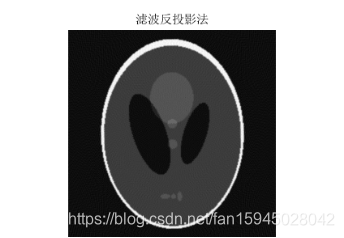

最后,通过对以上问题和数据以及成像图片的分析,觉的存在误差,成像模糊出现星形伪迹,从而最效果有很大的影响,本文通过滤波(卷积)反投影法对模糊图形进行滤波去噪使星形伪迹减弱甚至消失,然后对以上问题进行重新图像重建得到清晰的图形和结果,亦可以自己造模版进行检验,本文通过matlab自建模版进行模型验证分析,亦可得出清晰成像结果。

但是在计算过程中我们可以发现,由于角度的不同,这种叠加过程会使我们在原本没有介质存在的点计算出均值,影响准确度,形成重影,影响各个因素的判断。这种情况称之为星状伪迹。为了修正,我们在问题四中引入卷积反投影法,使所得数据与卷积因子相乘,通过计算,使投影数据值中正负数值相互抵消,根据系统显示的不同矩阵的大小,各投影滤过的原始数据被投影成像并显示出去掉晕伪影的清晰真实图像。

5.3问题四

5.3.1模型建立与求解

滤波处理模型:如上星状轨迹分析以说明误差和模糊产生原因本模型的目的就是为了将灰度像素矩阵中原本为0和不应该变化的使之变化了,出现边缘失锐效应,需要用对原来的灰度像素矩阵进行有效的滤波,使用滤波函数与灰度像素信号做叠

加运算处理,让灰度像素值再它两旁出现正和负成分,形成所谓的滤波灰度像素值,经过多次数值迭加,可让正和负几乎相互抵消,从而失锐效应消除,最后成像与原像更接近,这种滤波等效于将灰度像素矩阵第i列和进行卷积的到新的滤波矩阵第i列为。

滤波函数为第i列数据个数*2-1长度的一列数据,需要对该列进行设置数值以达到滤波的作用,首先都赋值为0,i为1到512,然后在进行详细设置如下:

{ (i为偶数)

{ (i为偶数)

{(i为奇数)

由滤波公式与原来灰度像素矩阵每一列进行卷积,得到了消除边缘失锐的灰度像素矩阵再用原本未滤波的模型进行图形重建运算,程序见附录程序四,结果以及效果如下:

图 14

图 15

图 16

反投影重建算法利用变换重建公式,能直接成像,速度较快,易于实现,对基函数的要求并不是很苛刻,但密度为0的点叠加后发生变化,即使修正也会引起成像的变化。而卷积反投影法对前期成像修正效果明显,使成像更清晰准确。该模型可用于工业,医学,生物,航天等多个领悟,为完成清晰准确的成像提供了较好的模型。